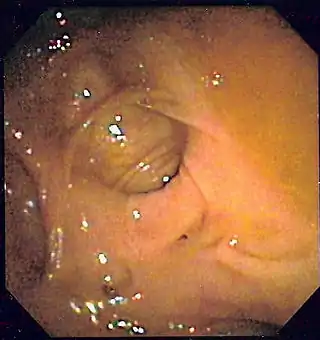

Colonoscopia

Es el método diagnóstico inicial más indicado para la mayor parte de los pacientes.[95][107] Consigue el diagnóstico entre el 75 y el 100% de los casos (con un 91% de media).[108] Y además ofrece la posibilidad de hacer tratamiento de la lesión. La potencia diagnóstica de la colonoscopia es mayor que la del resto de métodos diagnósticos radiológicos, ya que estos requieren que haya sangrado activo en el momento del examen.[17][4]

Para determinar la certeza de haber encontrado la localización o lesión de la hemorragia se aplican una serie de criterios diagnósticos endoscópicos, que están basados en los utilizados en la endoscopia de la HDA. Estos criterios vienen descritos en la tabla 4.

Tabla 4. Criterios diagnósticos endoscópicos de localización de la hemorragia en el colon (Zuckerman y Prakash 1998,[6] Green et al. 2005[113])

Grado de probabilidad Tipo Criterio

Definitivo 1 Lesión con hemorragia activa: visualización de emanación activa de sangre de un lugar específico o de una lesión fácilmente identificable, hemorragia que persiste a pesar de haber irrigado profusamente la zona.

Definitivo 2 Lesión no hemorrágica con vaso expuesto visible: lesión muy localizada protuberante de coloración púrpura o roja.

Definitivo 3 Lesión con coágulo adherido: coágulo denso y adherido que persiste a pesar de lavado profuso del mismo.

Presuntivo 4 Sangre reciente localizada en un segmento determinado del colon situado en la misma localización que una lesión potencialmente sangrante o distal a dicha lesión.

Presuntivo 5 Divertículo ulcerado con sangre reciente en una zona próxima.

Probable 6 Ausencia de sangre reciente en íleon terminal con sangre presente en el colon.

Como un alto porcentaje de hemorragias bajas ceden espontáneamente, hay muchos diagnósticos endoscópicos dudosos cuando no se identifica una lesión hemorrágica activa o un coágulo adherido evidentes. Es frecuente, por ejemplo, que se vean varios divérticulos y además una angiodisplasia, o unas hemorroides internas congestivas, sin signos de sangrado ni coágulo adherido en ninguna de estas lesiones. En ocasiones, será la presencia de sangre en un nivel u otro del colon junto con las lesiones potencialmente sangrantes lo que nos determine la impresión diagnóstica.[7]